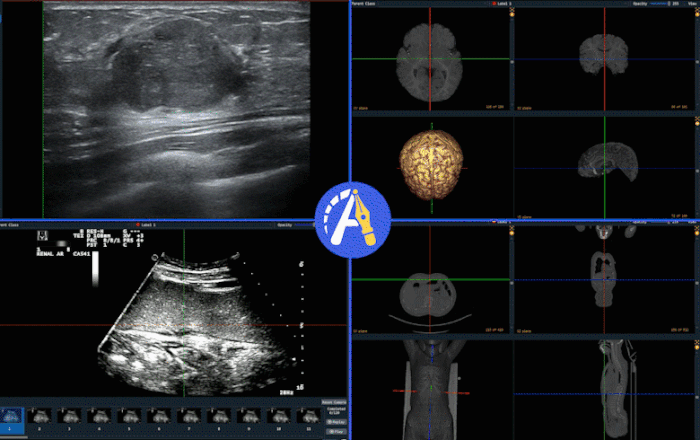

多模态影像互补标注

单一的影像模态使医生对病灶的定位和标注存在明显局限性。通过多模态信息的同步观察与互补使用,有利于医生准确标注病灶,如结合MRI中的T1与T2影像、多模态的超声影像、PET和CT影像、不同荧光染色的细胞涂片影像等。Pair提供的多模态影像互补标注功能可在标注过程同步显示不同模态的影像,降低医生对目标区域的定位和轮廓勾画的不确定度,有效帮助医生进行识别和标注。Pair提供的多模态标注功能可兼容二维、视频、三维和病理图像。